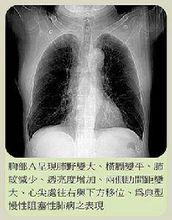

慢性阻塞性肺炎 阻塞性肺氣腫的診斷,尤其是早期診斷較不易,應結合病史、體徵、胸部X線檢查及肺功能檢查綜合判斷。凡有逐漸加重的氣急史,肺功能測驗示殘氣及殘氣/肺總量增加,第一秒用力呼氣量/用力肺活量減低,最大通氣量降低,氣體分布不勻,彌散功能減低;經支氣管擴張劑治療,肺功能無明顯改善,診斷即可成立。